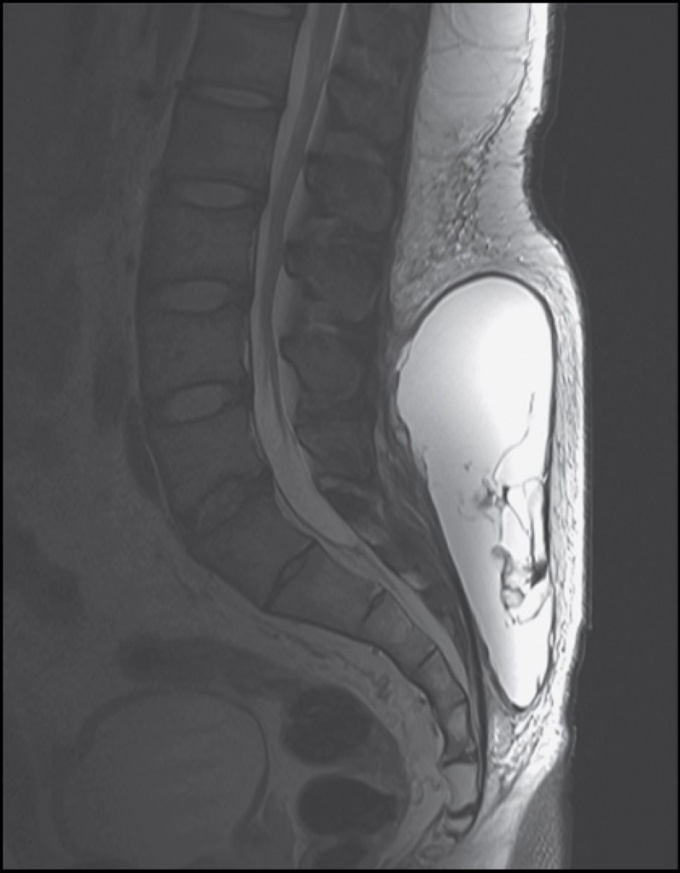

ÀÇ·áÁøÀº MRI °Ë»ç¸¦ ÅëÇØ Ç㸮 ¾Æ·¡ ºÎºÐ¿¡¼­ºÎÅÍ ¾ûµ¢À̱îÁö °¡·Î, ¼¼·Î, ±íÀÌÀÇ Å©±â°¡ °¢°¢ 20cm, 20cm, 10cm¿¡ À̸£´Â ÇǸ·ÀÌ Çü¼ºµÈ ³¶Á¾¼º Á¾±«¸¦ °üÂûÇßÀ¸¸ç, ÇÇÇÏ ¿¬ºÎÁ¶Á÷ÀÌ ±Ù¸·¿¡¼­ ¶³¾îÁ® ³ª°£ ºÎÀ§¿¡ »ïÃâ¹°ÀÌ °íÀÎ ¸ð·¼-¶ó¹ß¸® º´º¯À¸·Î Áø´ÜÇß´Ù.

º´º¯¿¡¼­ ÇǸ·ÀÌ Çü¼ºµÇ¸ç ¸¸¼ºÈ­µÅ ´Ù¸¥ Ä¡·á·Î´Â Àç¹ßÀÇ À§Ç輺ÀÌ ³ô´Ù´Â ÆÇ´Ü ÇÏ¿¡ ¼ö¼úÀû ÀýÁ¦¸¦ ½ÃÇàÇÏ°í ¼ö¼ú ÈÄ 3°³¿ù±îÁö Àç¹ßÀÌ ¾øÀ½À» È®ÀÎÇßÀ¸¸ç, ±Ù¼¶À¯¾Æ¼¼Æ÷·Î Çü¼ºµÈ °¡¼º³¶Á¾À̶ó´Â Á¶Á÷ÇÐÀû °Ë»ç°á°ú·Î ¸ð·¼-¶ó¹ß¸® º´º¯À¸·Î ÃÖÁ¾ Áø´ÜÇϰí, º´º¯ÀÇ Æ¯Â¡ÀûÀÎ ¿ÜÇü ¹× MRI ¼Ò°ßÀ» Çа迡 º¸°íÇß´Ù.